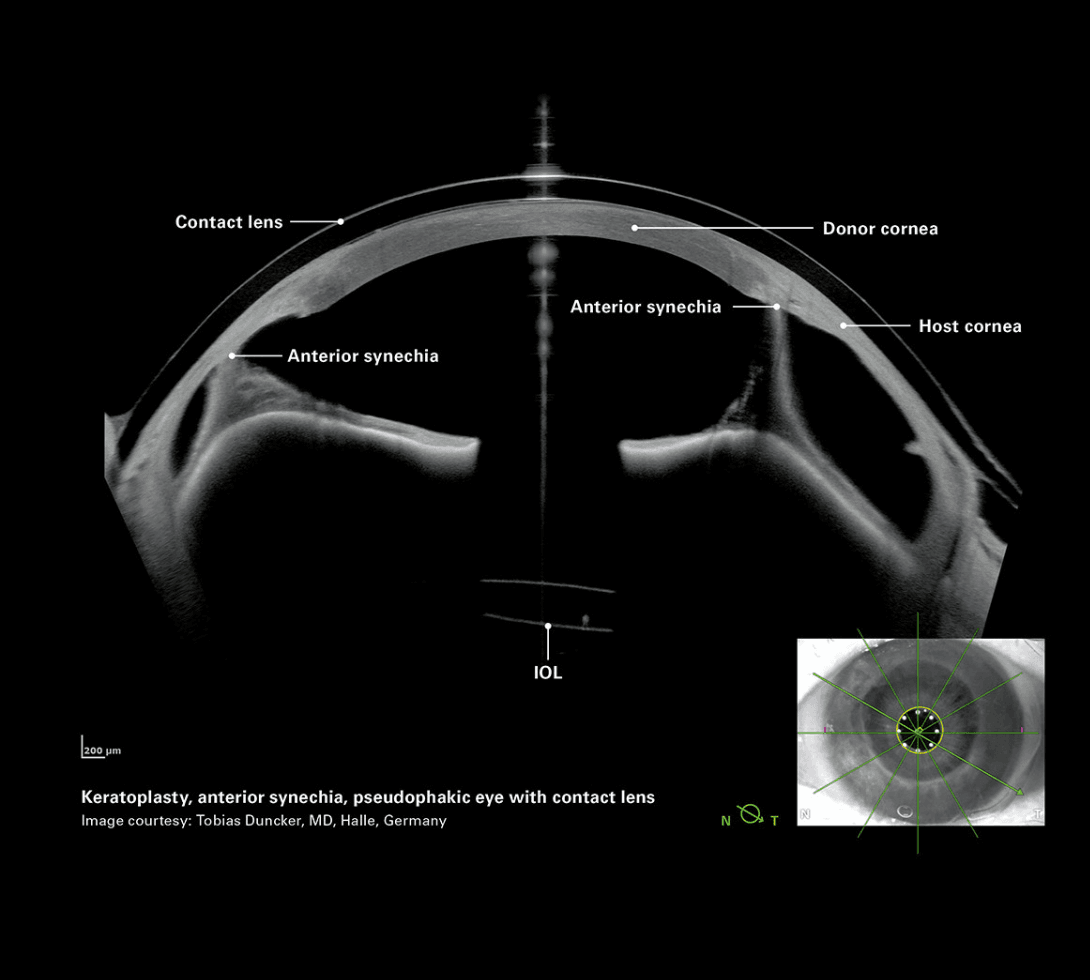

Trapianto con aderenze iride-cornea